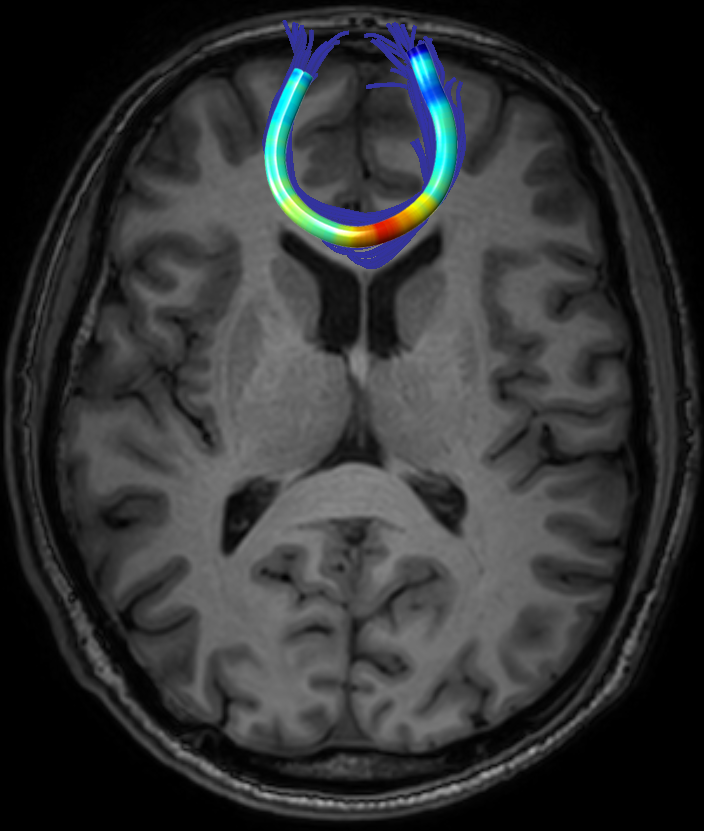

We performed pairwise comparison between two scans of a 32-year-old basketball player, diagnosed with mild occipital traumatic brain injury and frontal hemorrhage due to contrecoup impact, acquired one week and 6 months post-injury. The hemorrhagic lesion at the frontal right hemisphere of the player is no longer visible in the FLAIR image acquired 6 months after injury (Fig. 2a). Local differences between corresponding, longitudinal FA- and MD-FFDD profiles of the FMT (chosen due to its proximity to the lesion area) are shown in Fig. 2d. Figs. 2b-c present color-coded FMT to visually demonstrate these differences. Results show significant longitudinal variability at the right hemisphere part of the tract, corresponding to the lesion area, and relatively minor differences along the rest of the tract. These results should be considered as a proof of concept, validating the FFDD analysis results for the detection and localization of mTBI-related variabilities between fiber bundles.

| ONE WEEK | ![]() |

![]() |

FA-FFDD |

| 6 MONTHS | ![]() |

MD-FFDD |

| (a) FLAIR | (b) FA-FFDD | (c) MD-FFDD | (d) Local Differences |